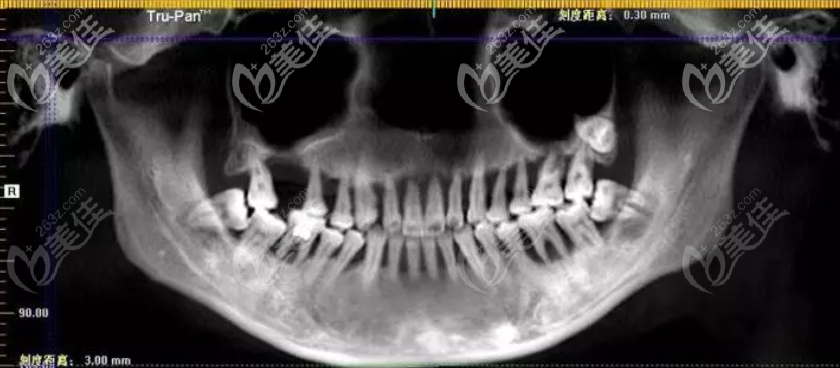

而导致她牙松动及功能丧失的是重度牙周炎,明明才22岁,但你说她80岁,或者90岁都不为过;为今后的生活质量考虑,她决定为自己做全口种植牙,只要能正常吃饭,多少钱都能接受。